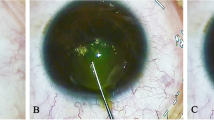

RTVue OCT and pentacam examination

CET was measured by RTVue-100 Fourier-domain OCT system (Optovue Inc., Fremont, CA,USA) and corneal maximum simulated keratometry (Km) was measured by Pentacam HR anterior segment analyzer (Oculus, Germany). The two instruments operated in a similar manner. All the operations were completed by trained skilled technicians in the dark room. The subject was seated, with jaw and forehead leaned against the headrest. During the measurement, the subjects opened their eyes as wide as possible and stared at the indicator light spot, and the examinations were completed without blinking. Pentacam operations were completed with quality specifications showing “OK”. OCT scan was automatically processed by RTVue-CAM software (Version 6.11; Optovue Inc.), providing the pachymetry (corneal thickness) map and indicated CT and CET ranges at the positions with radii of 0.0–1.0 mm (central zone), 1.0–2.5 mm (divided into eight quadrants) and 2.5–3.0 mm (divided into eight quadrants) from the corneal center, there were totally 17 regions per cornea (Fig. 1).